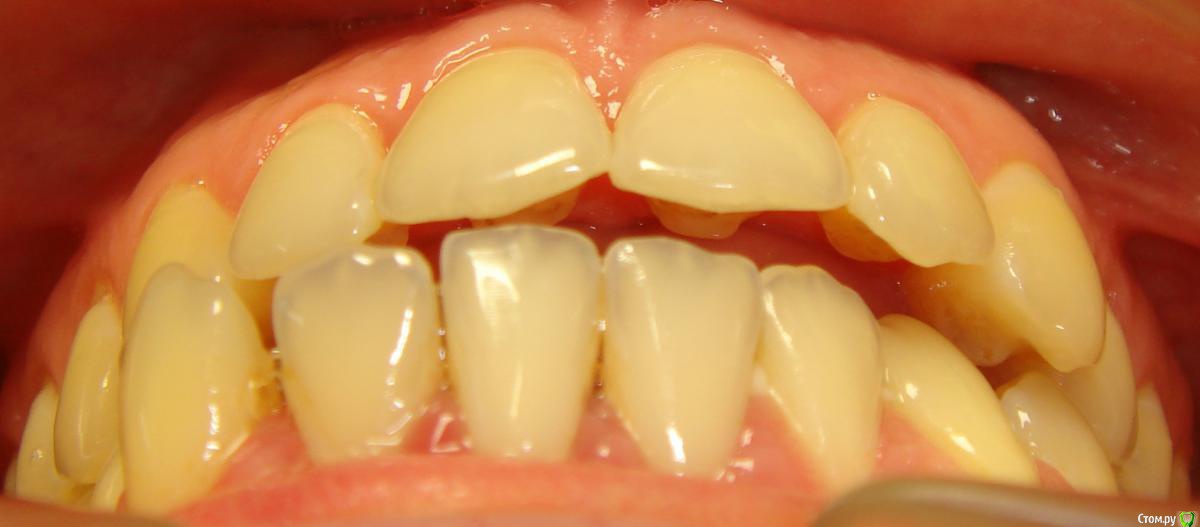

Opdihatop Опубликовано 4 марта, 2017 Поделиться Опубликовано 4 марта, 2017 И снова здравствуйте, коллеги. Вот такой вот случай к рассмотрению. Много лет назад пациентка уже проходила "камуфляжное" лечение. Со слов пациентки оно было закончено с передним открытым прикусом. Сейчас ситуация такая. Пациентка думает над ортохирургией, но меня смущает фронт н/ч. И по снимкам и по ситуации во рту корни 32, 31, 42, 43 зубов фенестрировали лингвальную кортикалку почти на всем протяжении, 33 - вестибулярную. Вопрос вот в чем: что делатьс этими зубами? Возможно ли их поставить на место? Или лучше не трогать, дольше простоят? Ссылка на комментарий

Opdihatop Опубликовано 4 марта, 2017 Автор Поделиться Опубликовано 4 марта, 2017 не трогать, в смысле вообще не трогать, даже хирургически. Боюсь потерять весь фронт н/ч Ссылка на комментарий